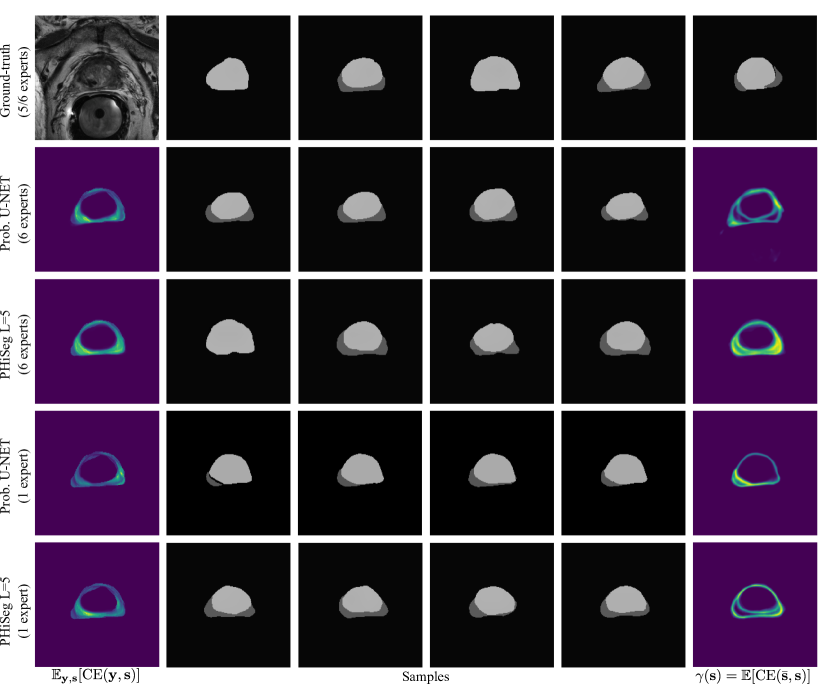

We evaluated the techniques in two experiments. First, we trained the methods using the masks from all available annotators, where in each batch we randomly sampled one annotation per image. We were interested in assessing how closely the distribution of generated samples matched the distribution of ground-truth annotations. To this end, we used the generalised energy distance where is 1 minus the intersection over union, i.e. , and are samples from the learned distribution , and ground-truth distribution [4]. The GED reduces the sample quality to a single, easy-to-understand number but, as a consequence, cannot be interpreted visually. Therefore, we additionally aimed to produce pixel-wise maps showing variability among the segmentation samples. We found the expected cross entropy between the mean segmentation mask and the samples to be a good measure, i.e. with the pixel position and the mean prediction. is statistically similar to variance with the L2-distance replaced by CE. However, we believe it is more suitable for measuring segmentation variability. Examples of our -maps along with sample segmentations are shown in Fig. 3. We quantify how well the -maps for each method predict regions with large uncertainty using the average normalised cross correlation (NCC) between the -maps and the CE error maps obtained with respect to each annotator:

We observed that when using all annotators for training, PHiSeg () produced significantly better and scores compared to all other methods. This can be observed qualitatively in Fig. 3 for a prostate slice with large inter-expert disagreements. Both, the prob. U-NET and PHiSeg () produced realistic samples but PHiSeg () was able to capture a wider variability. Furthermore, as indicated by the high values, PHiSeg’s () -maps were found to be very predictive of where in the image the method’s average prediction errors will occur. Similar results were obtained when training with only one annotator. We noticed that in this scenario the prob. U-NET may in some cases fail to learn variation in the data and revert back to an almost entirely deterministic behaviour (see fourth row in Fig. 3). We believe this can be explained by the prob. U-NET’s architecture which, in contrast to our method, allows the encoder-decoder structure to bypass the stochasticity. While our method also predicted smaller variations in the samples, they were still markedly more diverse. The lower performance of PhiSeg () indicates that using multiple resolution levels is crucial for our method. More samples for the prostate and LIDC-IDRI datasets can be found in Appendix B. From Tab. 1 it can be seen that no significant differences between the Dice scores were found for any of the methods (except PHiSeg’s ()), including the det. U-NET. From this we conclude that neither PhiSeg () nor the prob. U-NET suffer in segmentation performance due to their stochastic elements.

Appendix 0.B Additional Samples

Fig. 3 in the main article shows examples for a prostate with large inter-expert disagreements. In contrast, Fig. 0.B.1 is showing an example where the annotation disagreements were relatively smaller.